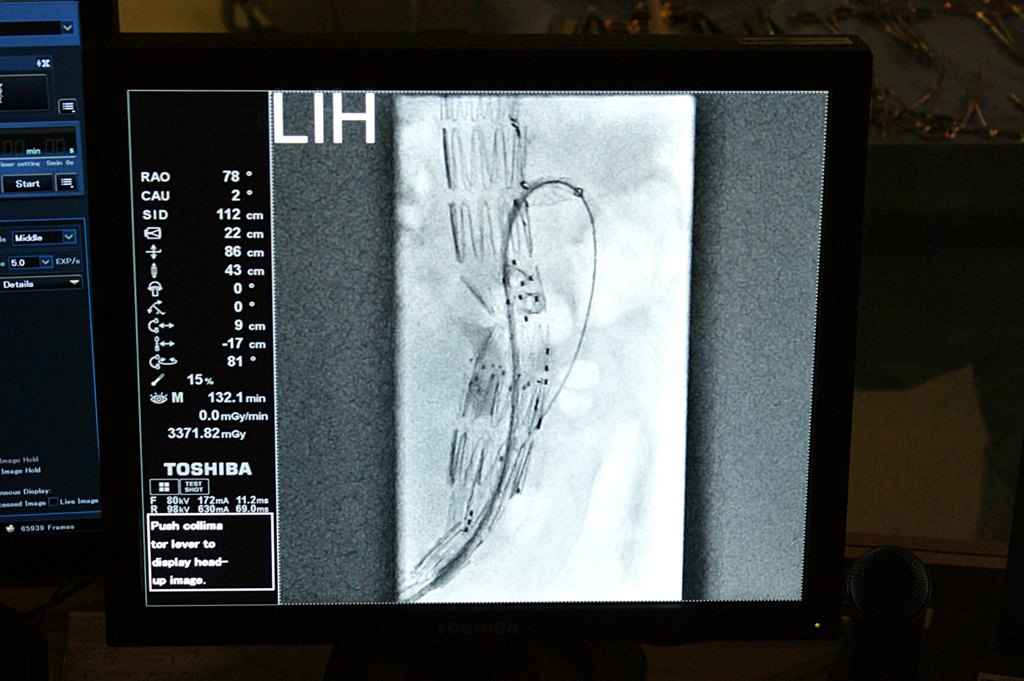

To zabieg jak przez "dziurkę od klucza" - lekarze Uniwersyteckiego Szpitala Klinicznego w Białymstoku przeprowadzili nowatorską - wewnątrznaczyniową - operację tętniaka aorty obejmującego tętnice brzuszne.

Do tej pory w Podlaskiem operowano tętniaki tylko metodą klasyczną. Jest to jednak bardzo ciężki i rozległy zabieg, który często kończył się śmiercią pacjenta.

Przygotowania do nowatorskiego zabiegu trwały kilka tygodni. Lekarze - do aorty dostali się przez pięciocentymetrowe nacięcia w pachwinach. Oprócz kompleksowych badań, trzeba było przygotować specjalną protezę szytą na miarę w Nowej Zelandii. Pacjent czuje się dobrze, szybko wraca do zdrowia.

Nowej metody operowania białostoccy lekarze uczą się od prof. Piotra Kasprzaka z Kliniki Chirurgii Naczyń Szpitala Uniwersyteckiego w Regensburgu. Lekarze mają nadzieję, że tego typu zabiegi będą stale wykonywane w Białymstoku. Problemem jest cena protez. Wszystko kosztuje około 200 tys. zł.